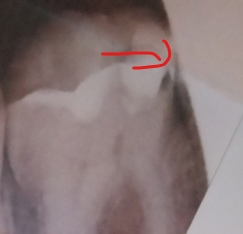

Алешка Опубликовано 5 сентября, 2024 Поделиться Опубликовано 5 сентября, 2024 (изменено) Периодически хожу и проверяю зуб, чтобы проверить, не увеличилась ли киста или что-то типа того (в терминах не разбираюсь). Советовать перелечивать зуб не надо, так как гарантии, что он и дальше будет нормальным, нет, а я не настолько богат. Мне проще удалять. Так вот, сделав вчера снимок, я обнаружил на нем какие-то штуки (на скрине выделил). Это что? Раньше делал снимки и такого не было. Плюс делал 3d снимок, посмотрев на который, врач сказал, что мне хорошо пролечили каналы. А на этом скрине выглядит так, будто там что-то в каналах... Или это просто такой снимок? Изменено 5 сентября, 2024 пользователем Алешка Ссылка на комментарий

АнтонТЛТ Опубликовано 5 сентября, 2024 Поделиться Опубликовано 5 сентября, 2024 В этом корне 2 канала, разные ракурсы снимков. На нижнем один канал прячется за другой. На верхнем не прячется, поэтому темная полоса по середине. Если об этом идёт речь. Ссылка на комментарий

Алешка Опубликовано 5 сентября, 2024 Автор Поделиться Опубликовано 5 сентября, 2024 19 минут назад, АнтонТЛТ сказал: В этом корне 2 канала, разные ракурсы снимков. На нижнем один канал прячется за другой. На верхнем не прячется, поэтому темная полоса по середине. Если об этом идёт речь. Вот про это речь Ссылка на комментарий

Carioznik Опубликовано 5 сентября, 2024 Поделиться Опубликовано 5 сентября, 2024 27 минут назад, Алешка сказал: Вот про это речь Вам Антон про это и написал. Разные ракурсы двухмерных изображений, поэтому кажется, что появились изменения. 2 часа назад, Алешка сказал: Но зато тут видно кисту, которую, кстати, не видно на новом снимке почему-то. Может прошла) Не прошла, и кстати и на новом видно, но опять же, из-за другого ракурса уже не так явно видно. Для оценки динамики -прицельные снимки не годятся(каждый раз, ракурс будет разный и картинка, соответственно, тоже), нужно делать КТ и сравнивать старую и новую КТ между собой. Ссылка на комментарий